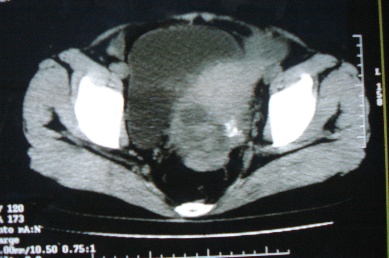

ct10755,女,48岁。感腹胀一周入院。

考虑右侧卵巢囊腺癌并腹腔转移、子宫肌瘤

支持右侧卵巢囊腺癌并腹腔转移

考虑右侧卵巢囊腺癌并腹腔转移可能性大、子宫肌瘤

支持:右侧卵巢囊腺癌并腹腔转移,或囊腺瘤破裂腹腔种植。

支持:右侧卵巢囊腺癌并腹腔转移、腹水、盆腔积液。

考虑为右侧卵巢囊腺癌并腹腔转移、腹水、盆腔积液.

右侧卵巢囊腺癌并腹腔转移,腹水。

支持右侧卵巢囊腺癌并腹腔转移(大量腹水)。